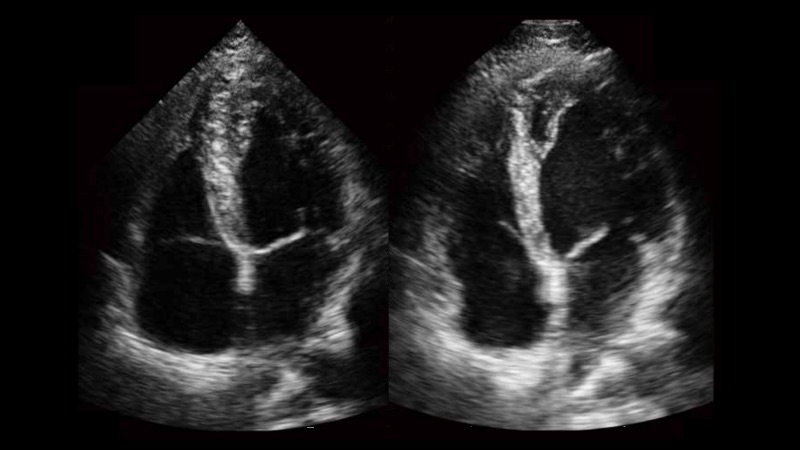

自動識別前后壁內(nèi)膜厚度,為心血管疾病早期評估提供快速準確依據(jù)。

自動識別收縮和舒張末期心肌內(nèi)膜,自動計算射血分數(shù)EF值。